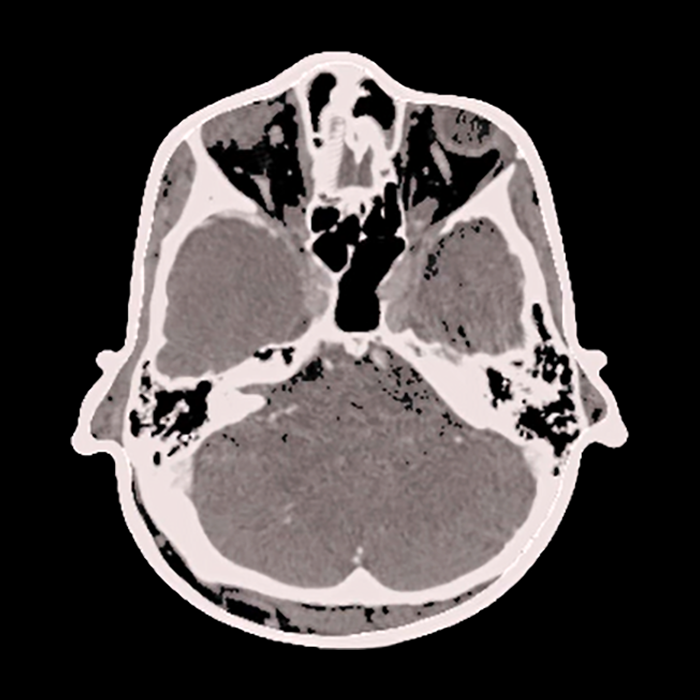

The user interface was custom designed to leverage the power of the software tools in a form which is intuitive and user friendly and provides the key clinical functionality. During the planning stage, for example, the user is walked through tasks such as skin segmentation, lesion and trajectory delineation, and landmark selection to be used for registration.

Pre-op Planning

Skin Segmentation

Target Segmentation

Trajectory Planning